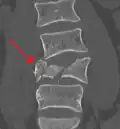

A burst fracture of L4 as seen on CT -

A burst fracture of L4 as seen on CT